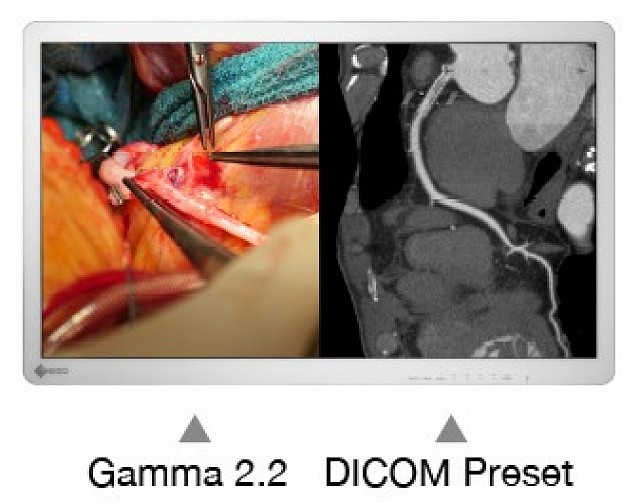

具有4K UHD(3840 x 2160像素)分辨率和高亮度的32英寸宽屏手术监视器。

EX3241具有4K UHD(3840 x 2160像素)分辨率和高亮度的32英寸宽屏手术监视器。

输入端口切换、亮度、灰阶曲线、色域等各种设置,都可以作为预设功能存储在监视器中。可以根据用户的偏好通过屏幕菜单来命名这些设置。